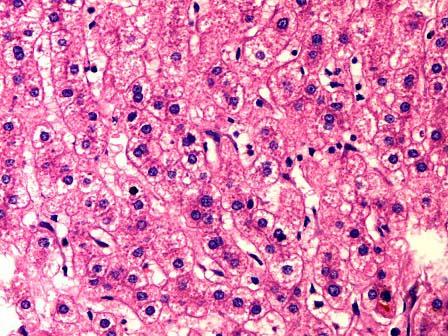

问题 男性死者,尸检时见肝脏肿大,包膜紧张。切面红褐色。镜检如图所示,主要病变有 ( )

选项 A.肝细胞水肿 B.肝细胞脂肪变性 C.间质玻璃样变性 D.假小叶形成 E.碎片状坏死

答案 A